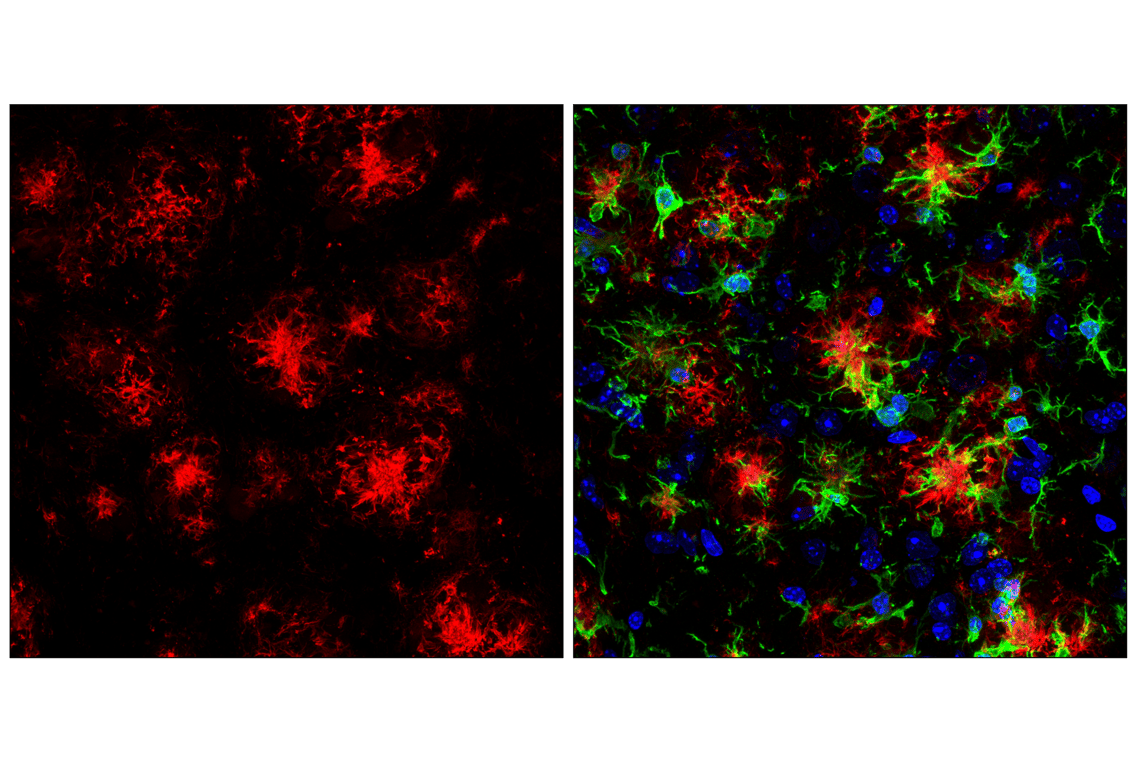

beta-Amyloid (D54D2) Horse Chimeric Monoclonal Antibody recognizes endogenous levels of total β-amyloid peptide (Aβ). This antibody detects several isoforms of Aβ, such as Aβ-37, Aβ-38, Aβ-39, Aβ-40, and Aβ-42. This product detects transgenically expressed human APP in mouse models.

Immunofluorescence (Frozen) 1:50 - 1:200